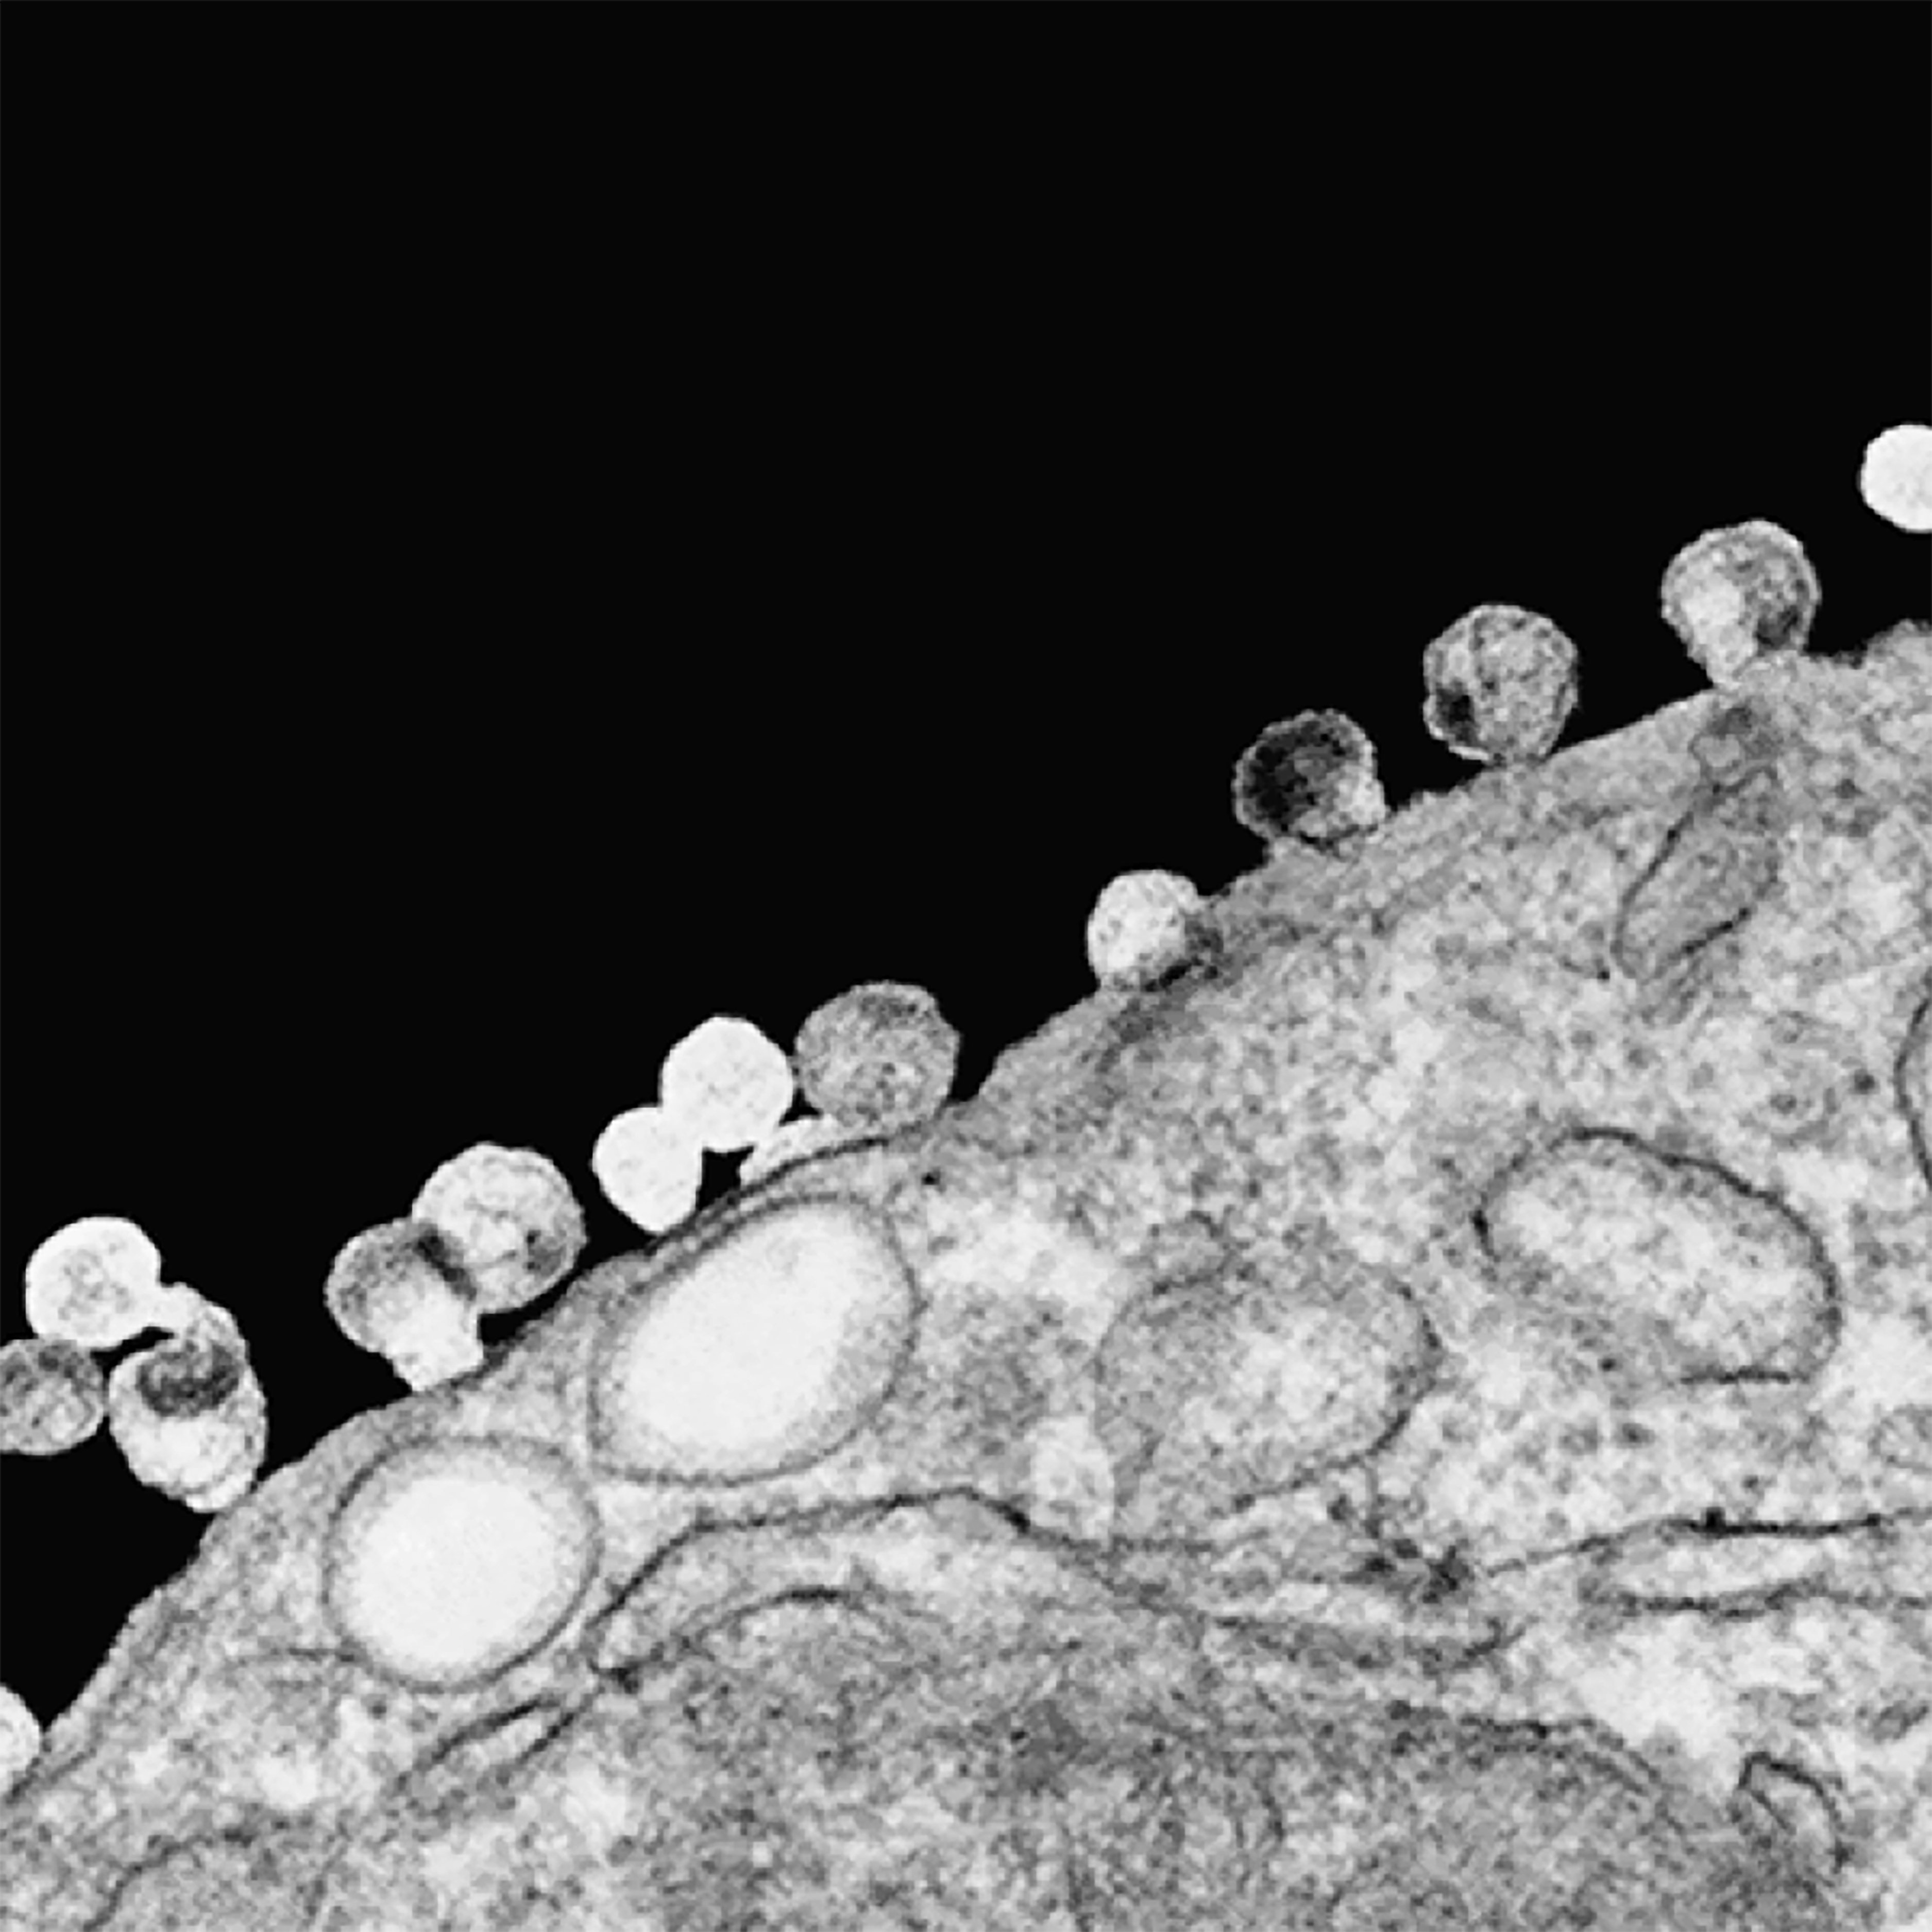

As a result of this technical limitation, I changed the frame of the disease interaction design from room-scale to body-scale. Inspired by the image of viral budding (Figure 17), I started with the concept that shadowpox infection was transmitted by one person’s shadow falling across another’s, where it incubated in the shadowed side of the new host’s body, then eventually “budded” out of this “dark side of the moon” to migrate into the lighted side.

Figure 17. R. Dourmashkin (Wellcome Images), HIV particles budding from the surface of a T cell, 2004. Wellcome Images available under the following creative commons usage http://creativecommons.org/licenses/by-nc-nd/2.0/uk/; http://www.cellimagelibrary.org/images/39465.